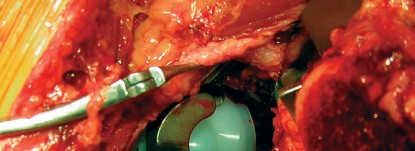

في جراحة استبدال مفصل الورك الكلي، يتم استبدال رأس عظم الفخذ التالف بمكون معدني كروي، ويتم استبدال الحُق الطبيعي المتضرر بمكون حُقي صناعي. المكون الحُقي الأسمنتي هو عبارة عن كوب معدني أو بلاستيكي عالي الجودة (عادة من البولي إيثيلين) يتم تثبيته داخل تجويف الحُق في عظم الحوض باستخدام "الأسمنت العظمي" (Bone Cement)، وهو مادة بوليمرية حيوية تعمل كغراء قوي لتثبيت المكون بشكل فوري ومستقر.

- المكونات الأسمنتية (Cemented Components): تُثبت في العظم باستخدام أسمنت العظم (Bone Cement)، وهو بوليمر سريع التصلب يوفر تثبيتًا فوريًا ومستقرًا.